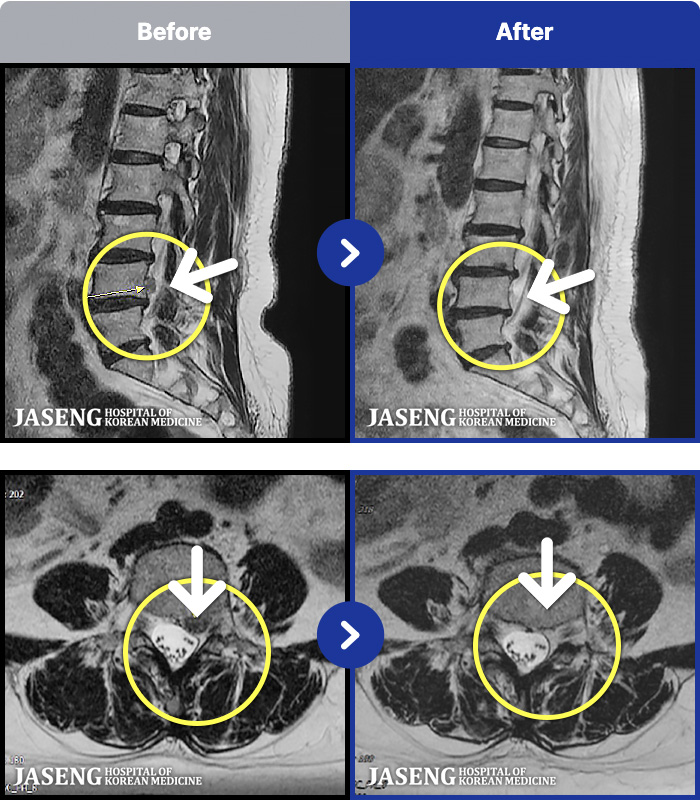

1,257 MRI ũ ʸ Ȯϼ.